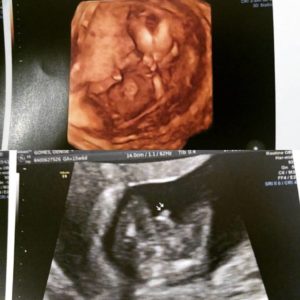

Com relação aos cuidados com saúde e seguimento do Pré Natal, nesse mês fiz pouca coisa. Fiz um exame de Ultrassom Obstétrico na 16ª semana, no qual conseguiu confirmar que estou esperando um menininho! Fiz uma consulta médica de rotina, que constatou estar tudo bem comigo. E mantive o uso das vitaminas que estava usando, com exceção do ácido fólico que já suspendi.